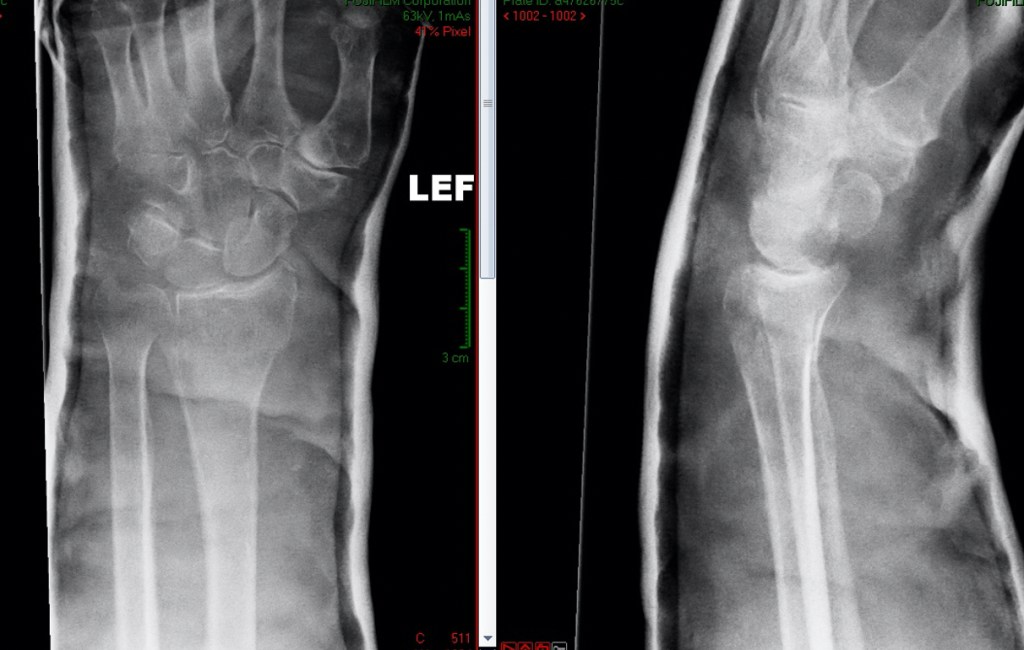

Where is the distal radius?

The distal radius is an area of the forearm bone located next to the wrist joint. The two forearm bones are the radius and ulna. They articulate at the elbow with the humerus bone, and at the wrist with the carpal or wrist bones. These two bones also form joints with each other at both the elbow and the wrist to allow the forearm to rotate. The distal radius is the term given to the area of the radius bone within 2-3cm of the wrist joint.

Fractures of the distal radius occur usually with a fall onto the outstretched hand. Often, the tip of the ulna will fracture at the same time.

2) UNSTABLE INJURY When the injury is unstable, it means that the broken parts of the bone do not move together, and often there is a gap on the xray between the bone ends, or an abnormal angulation between the bone ends.